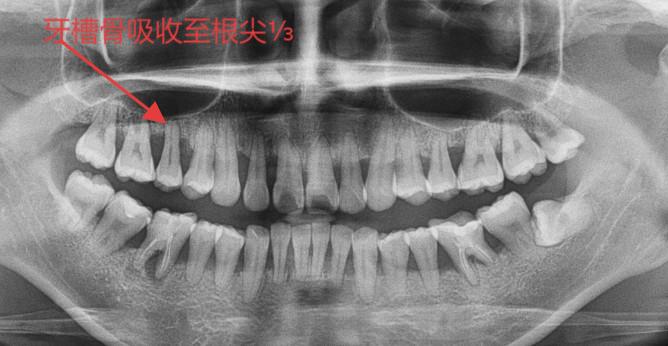

口腔科医生一检查,好家伙!牙龈红肿得像成熟的车厘子,牙齿之间的牙龈已经“萎缩”,用探针一探,居然能插进牙齿和牙龈之间(这就是“牙周袋”),X线片显示:支撑牙齿的牙槽骨已经被“吃掉”了1/3!

更可怕的是,牙周组织一旦破坏,无法再生。比如李先生的牙槽骨已经吸收了1/3,即使治疗,也只能阻止进一步破坏,无法让骨头长回来。